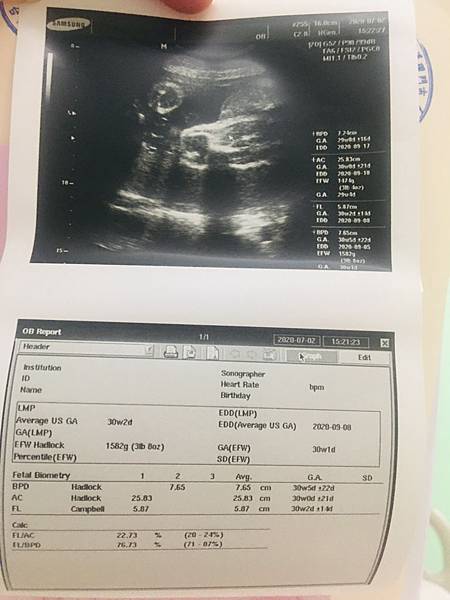

今天下午終於坐著輪椅被推去門診照超音波了,其實從昨天醫生巡房說要安排今天陰道超音波時就開始微微緊張,感覺那天內診的陰影還在啊!還好後來醫生還是用腹部超音波,寶寶也都健康成長中,體重有1582g囉,就是頭部已經入骨盆不願出來,醫生說這不影響寶寶生長,主要是怕站著或坐著時壓迫到,讓子宮頸變短,所以除了廁所外,其他時間都要躺著,接下來會再加用黃體素盡量幫忙子宮頸撐住,子宮頸目前長度只有1.88公分!